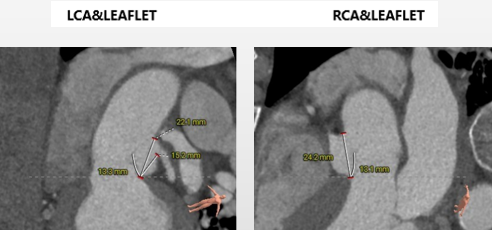

• 左右冠脉开口高度可,瓣叶长度均小于冠脉开口下缘到瓣叶附着缘位置,左冠脉可见少量散在钙化。

主动脉根部评估:

• 瓣环 周长79.7mm,平均周长径25.4mm

• SOV瓦式窦 34.4mm * 37.4mm * 39.2mm

• LVOT 周长83.1mm,平均周长径 26.5mm

• STJ 周长104.9mm,平均周长径 33.4mm,高度27.7mm

• 升主动脉 直径37.6(40mm高度)

冠脉高度、瓣叶长度及左室内径:

冠脉高度可,未见冗长瓣叶,左室内偏径大,横位心(71°)